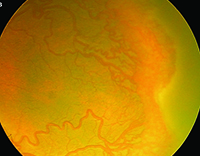

The greatest impact of WF imaging has been in pediatric retina. ROP surveillance with RetCam has proved so effective that many centers utilize nurse practitioners to capture images, which the screening ophthalmologist then reviews (Figure 1). This approach had been validated as early as 2001 and has since been replicated.3![]() | ![]() |

| Figure 1. RetCam images of a premature infant screened for retinopathy of prematurity (ROP) show stage 3 ROP in zone 1 (A) and more peripheral stage 3 ROP in zone 2 (B). | |